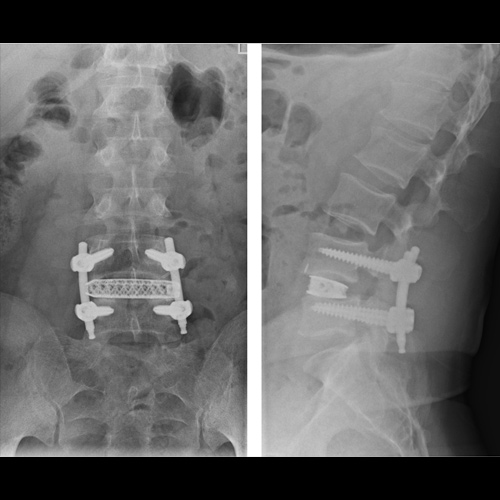

Spinal stenosis (Lumbar) Spinal stenosis (Cervical) Spinal stenosis (Thoracic) Lumbar Disc Herniation Spondylolisthesis Cervical Foraminal Stenosis Vertebroplasty Lumbar Fusion Anterior Cervical Fusion (ACDF) Posterior Cervical Fusion Thoracic Fusion Revision Lumbar Fusion Surgery Facet Joint Cyst Spinal Tumour Minimally Invasive Lumbar Fusion (XLIF) Minimally Invasive Lumbar Fusion (ALIF) Lumbar Fusion (TLIF) Thoraco-lumbar Fusion Lumbar Corpectomy Complex Lumbar Spine Surgery (Spino-pelvic fixation) Complex Cervical Spine Surgery Complex Thoracic Spine Surgery Occipito-cervical Fusion Minimally invasive surgery for thoracic disc herniation Other Related Topics